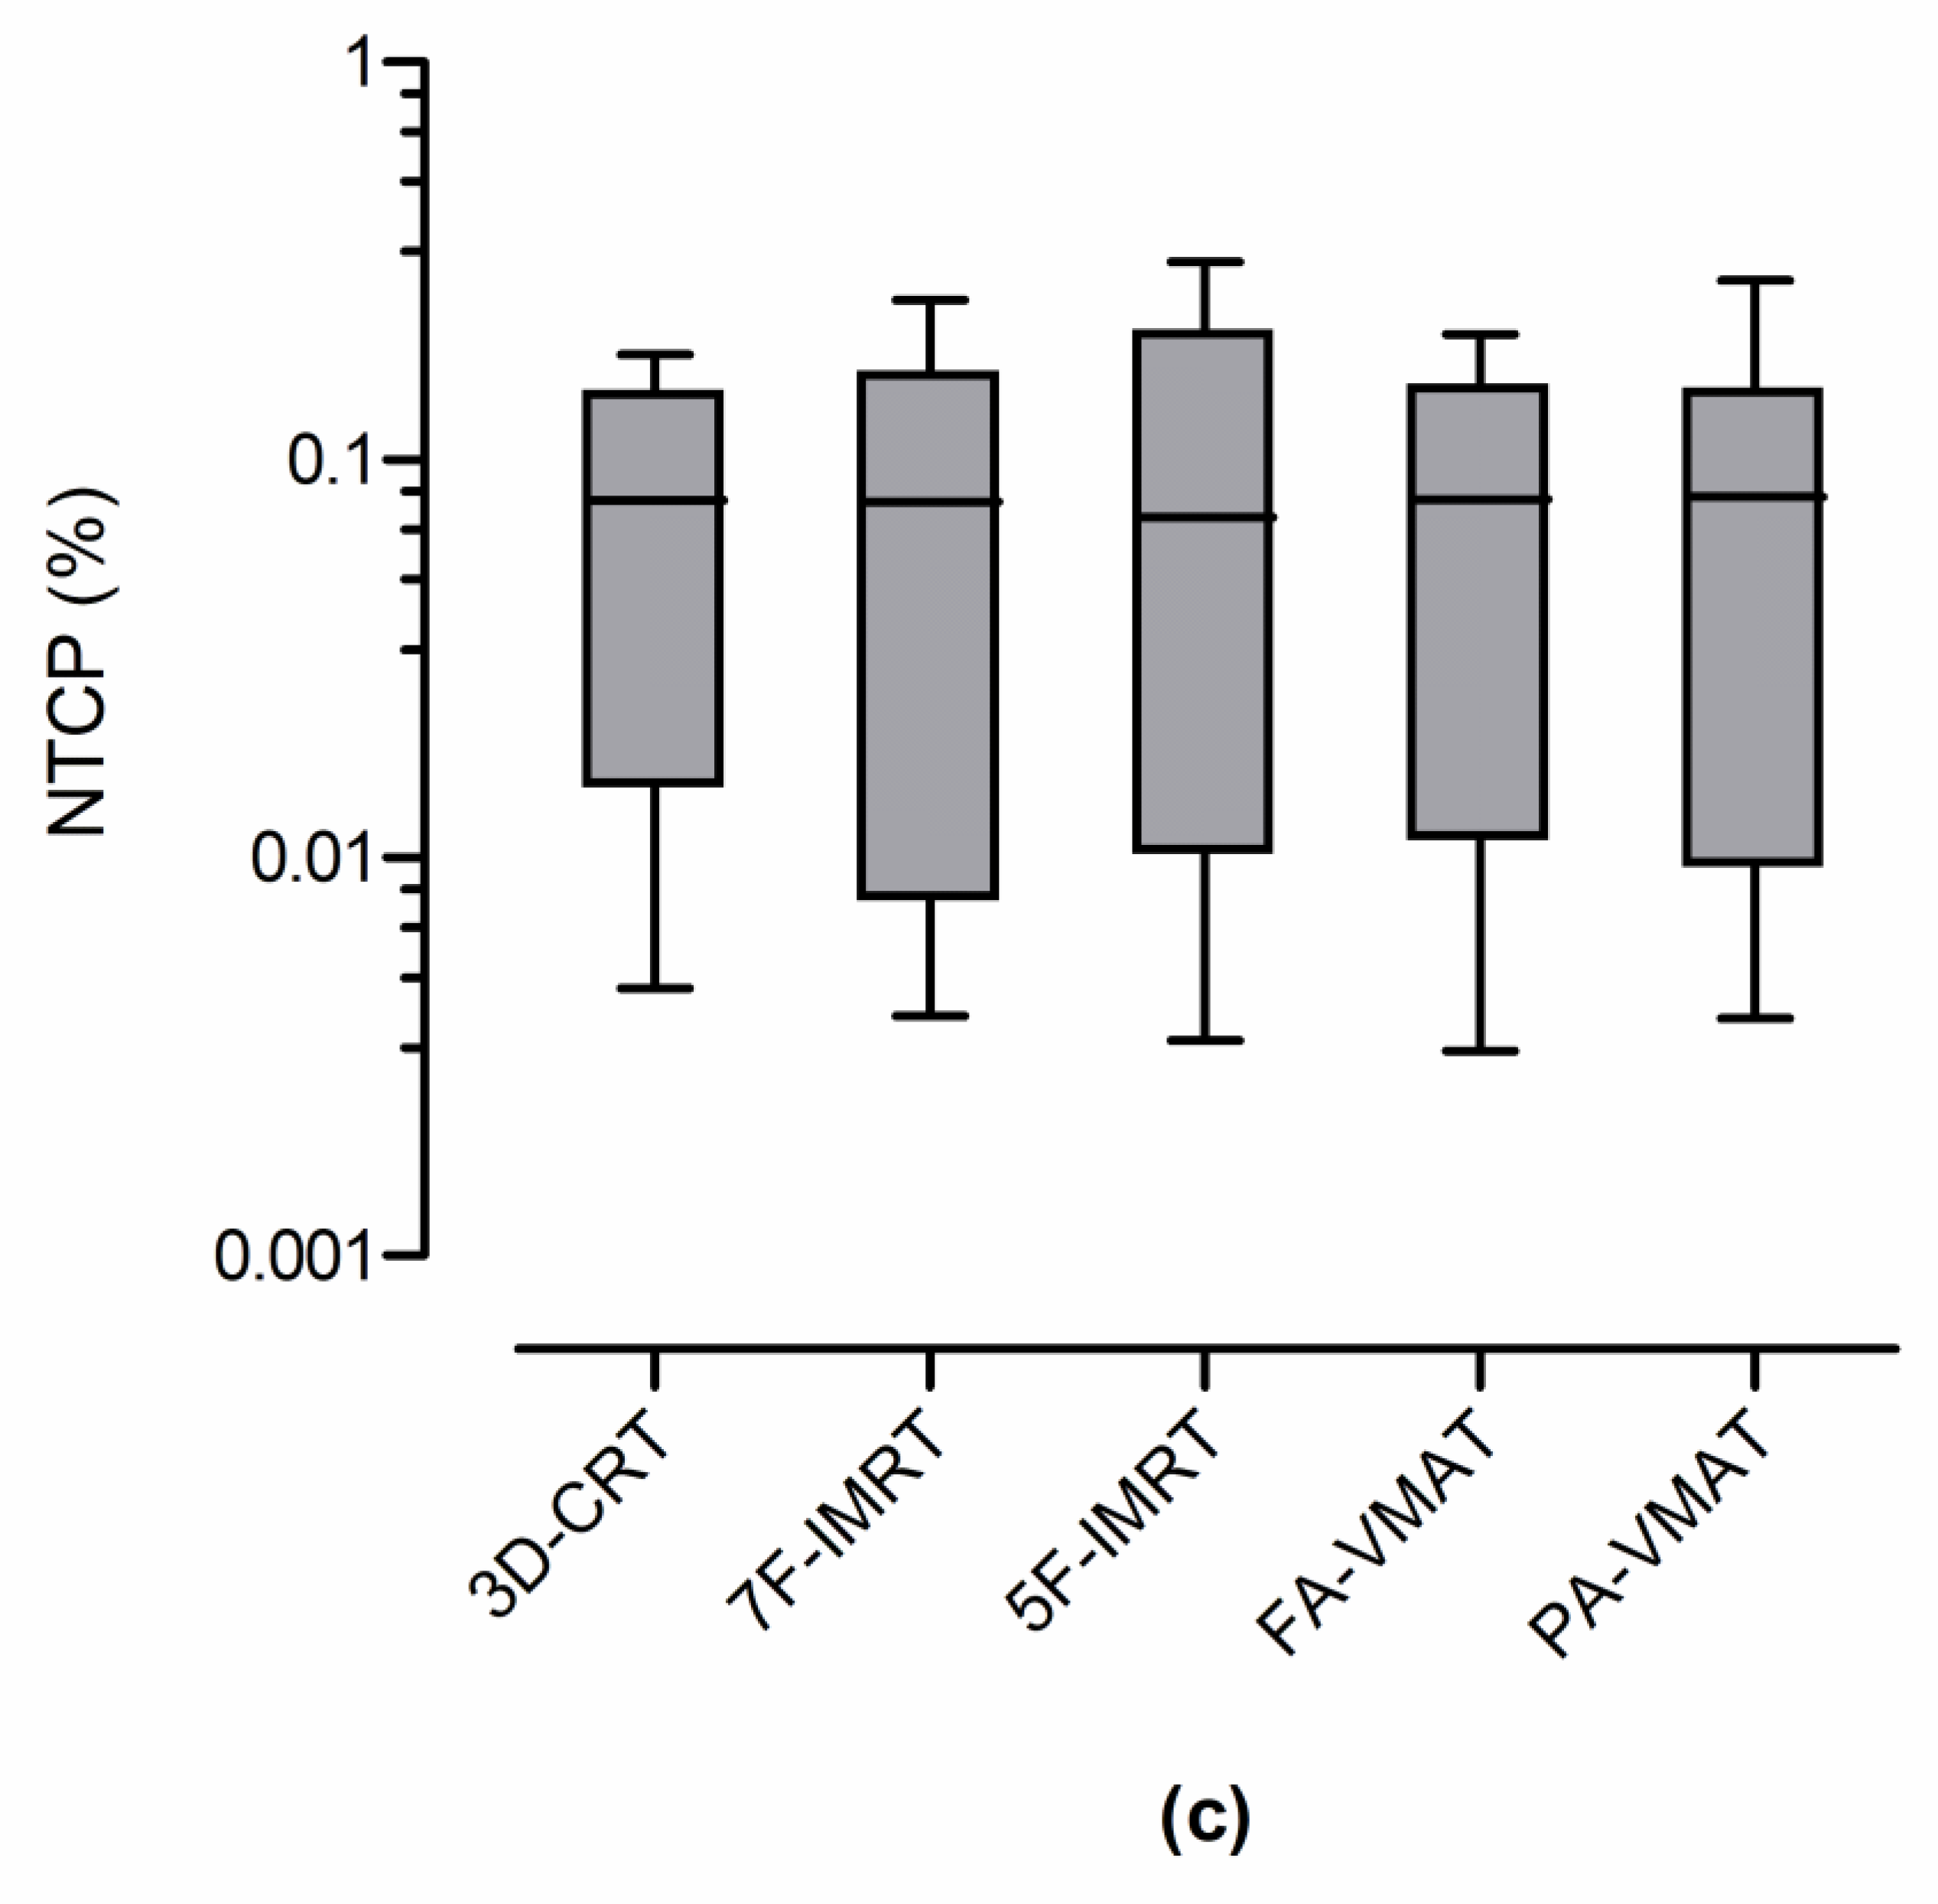

3.2. Radiobiological Parameters

| Technique | NTCP (%) | ||

|---|---|---|---|

| Lungs | Heart | Esophagus | |

| 3D-CRT | 0.38 ± 0.44 | 0.06 ± 0.11 | 0.08 ± 0.07 |

| 7F-IMRT | 0.34 ± 0.46 | 0.04 ± 0.07 | 0.09 ± 0.09 |

| 5F-IMRT | 0.39 ± 0.62 | 0.03 ± 0.06 | 0.10 ± 0.11 |

| FA-VMAT | 0.43 ± 0.57 | 0.03 ± 0.06 | 0.09 ± 0.07 |

| PA-VMAT | 0.49 ± 0.72 | 0.04 ± 0.07 | 0.09 ± 0.09 |